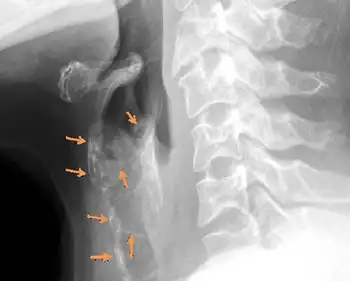

Being an extremely rare autosomal genetic disorder, differential diagnosis has only led to several cases since 1972. Initial diagnosis lends itself to facial abnormalities including sloping forehead, maxillary hypoplasia, nasal bridge depression, wide mouth, dental malocclusion, and receding chin.[5] Electroencephalography (EEG), computed tomography (CT) scanning, and skeletal survey are further required for confident diagnosis. Commonly, diffuse cartilage calcification and brachytelephalangism are identified by X-radiation (X-ray), while peripheral pulmonary arterial stenosis, hearing loss, dysmorphic facies, and mental retardation are confirmed with confidence by the aforementioned diagnostic techniques.[8]

Diagnosis is often confirmed by several abnormalities of skeletal origin. There is a sequential order of findings, according to Cormode et al., which initiate in abnormal cartilage calcification and later brachytelephalangism.[9] The uniqueness of brachytelephalangy in KS results in distinctively broadened and shortened first through fourth distal phalanges, while the fifth distal phalanx bone remains unaffected.[10] Radiography also reveals several skeletal anomalies including facial hypoplasia resulting in underdevelopment of the nasal bridge with noticeably diminished alae nasi. In addition to distinguishable facial features, patients generally demonstrate shorter than average stature and general mild developmental delay.

Many common effects sharing similarity with chondrodysplasia punctata stem from cartilaginous origin. Radiography reveals extensive diffuse cartilaginous calcification. Pulmonary angiography and soft tissue radiography often demonstrate significant cartilaginous ossification in the trachea and larynx, with perichondral and endochondral centers significantly ossified in transformed cartilage.[11] Abnormal diffuse cartilaginous ossification is typically most pronounced in the auricles and cartilage of the trachea and larynx, while peripheral pulmonary stenosis is frequently common in KS. In consanguineous parents of children with KS, one is often phenotypically normal, while the other is positive for pulmonary stenosis. Perhaps emanating from diffuse laryngotracheal calcification, patients often present with recurrent respiratory infection, otitis media, and sinusitis.[12]